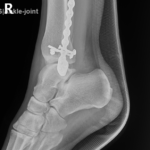

if the fracture is displaced, surgery may be needed to put the bone back into the correct position and fix the bone with Plates & screws or nails for adequate healing to occur.

- Ankle Fractures.